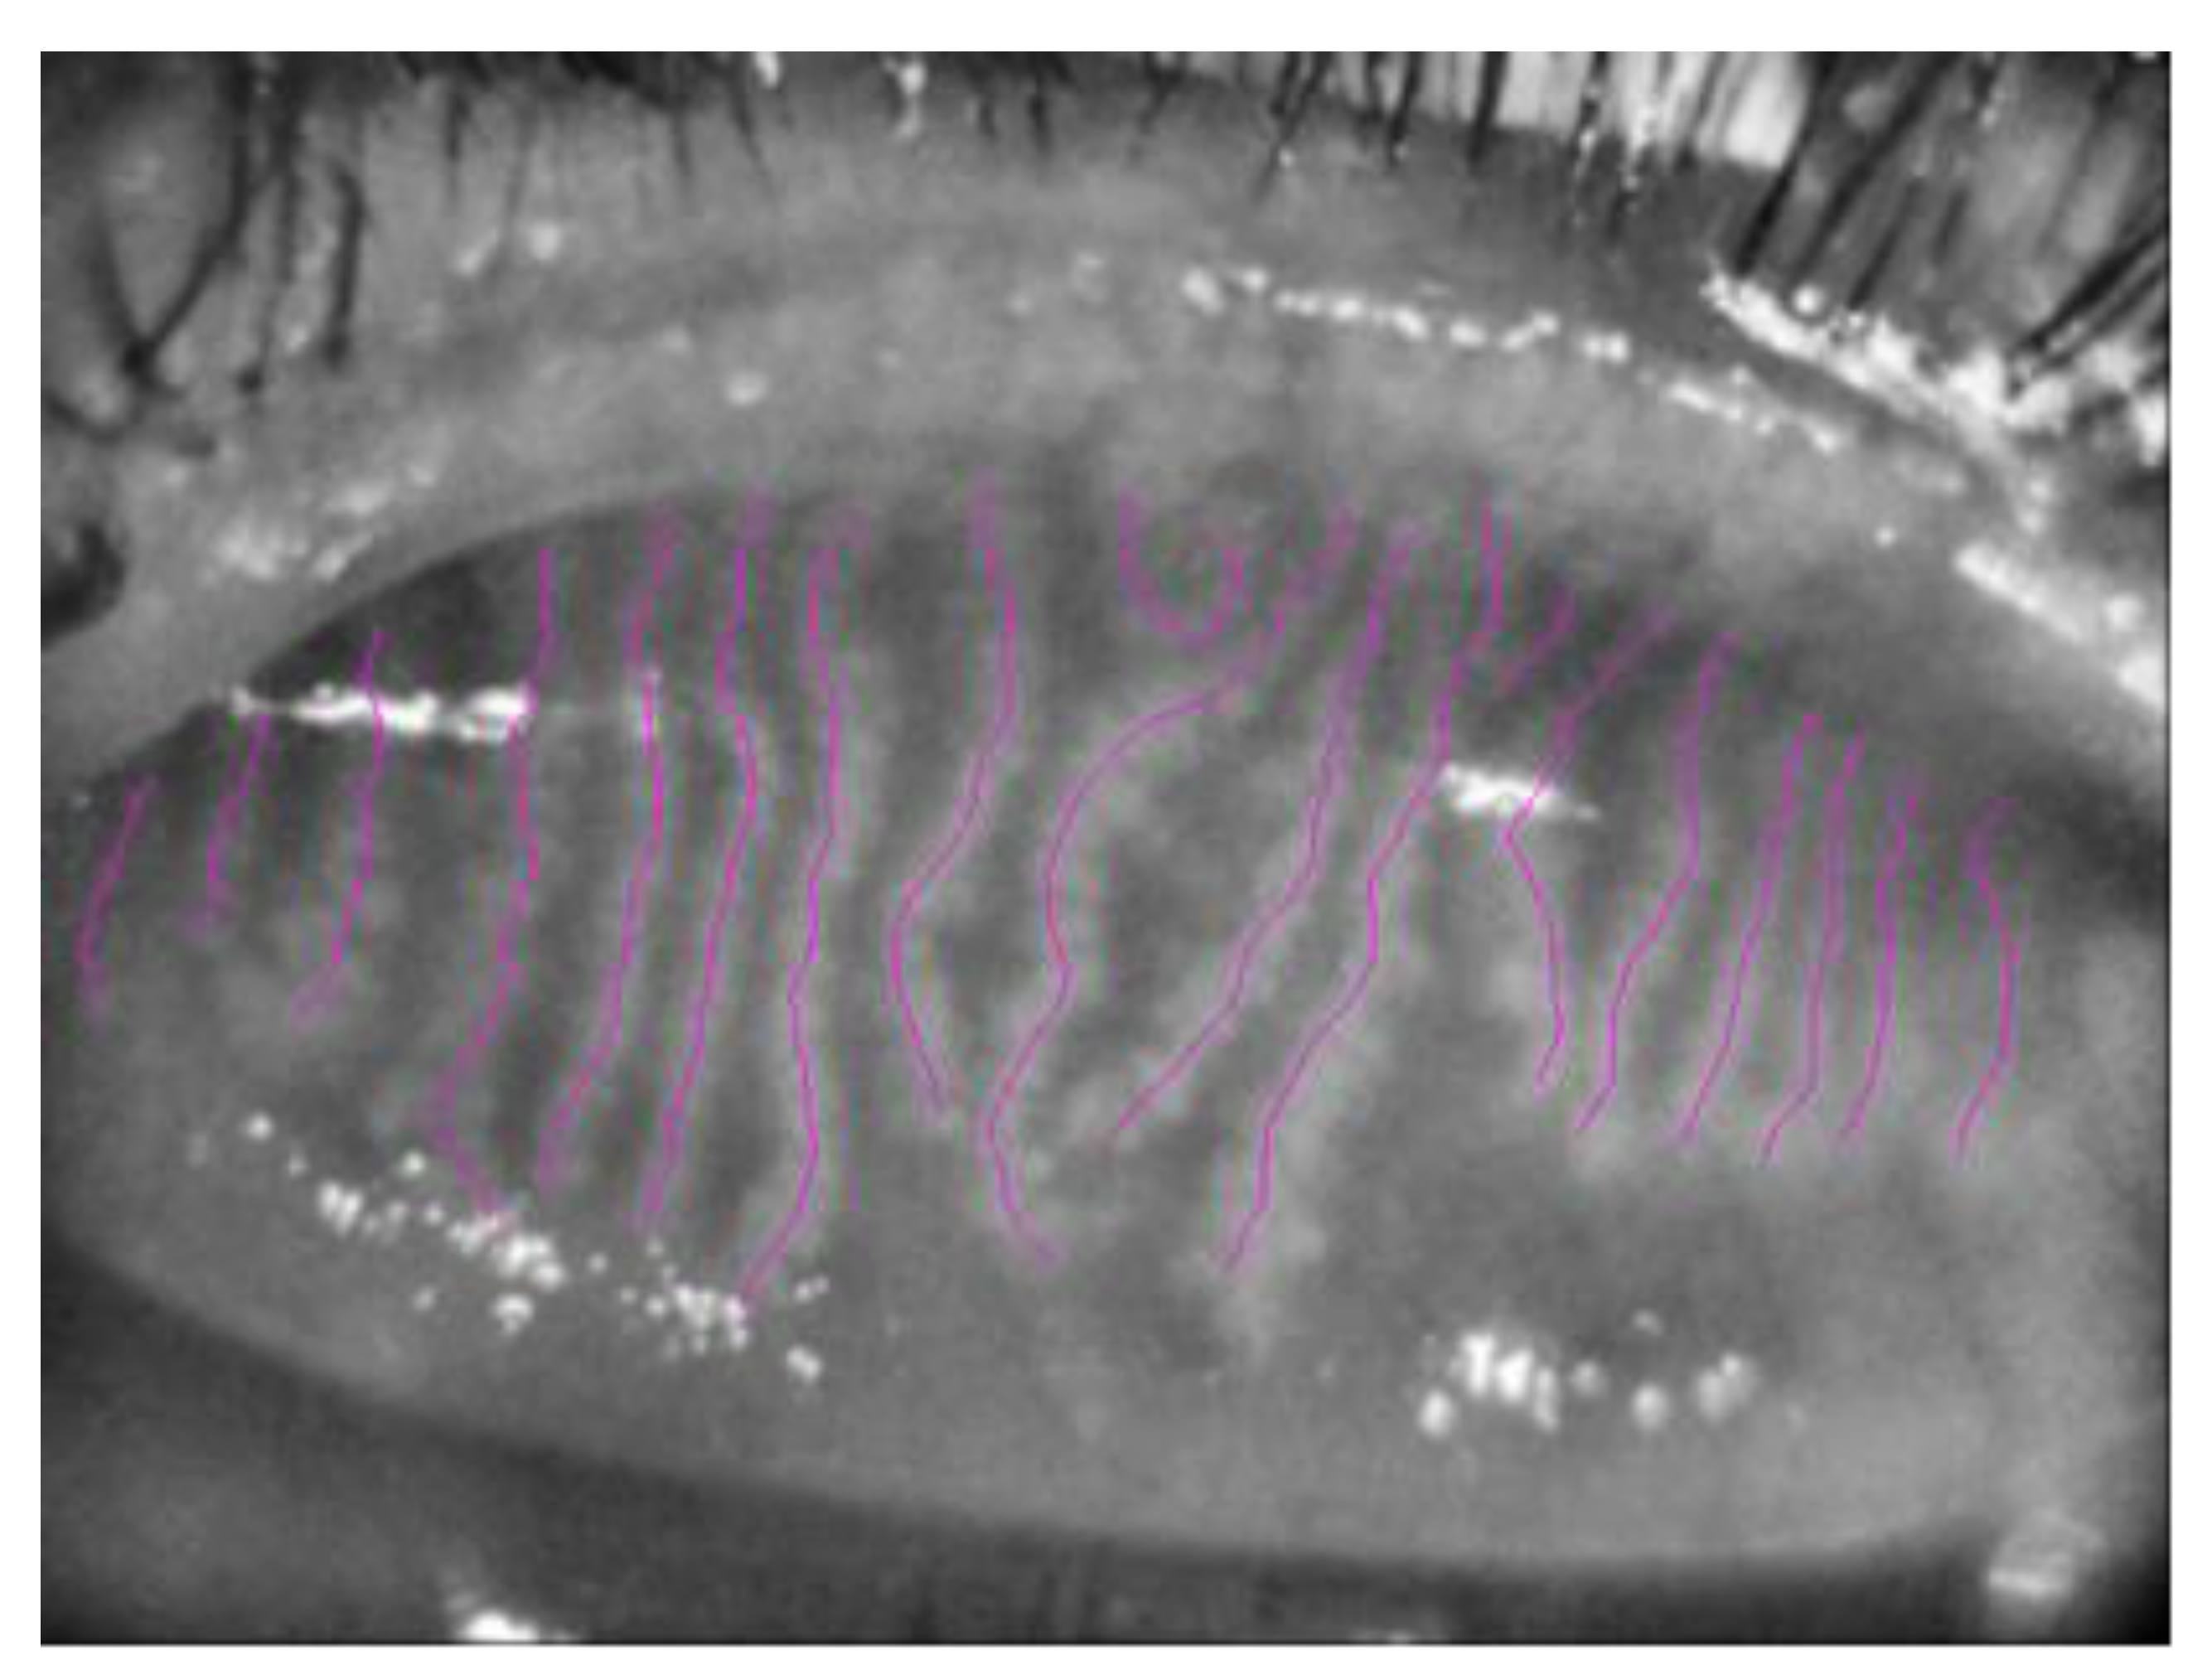

3.2. Meibography Analysis